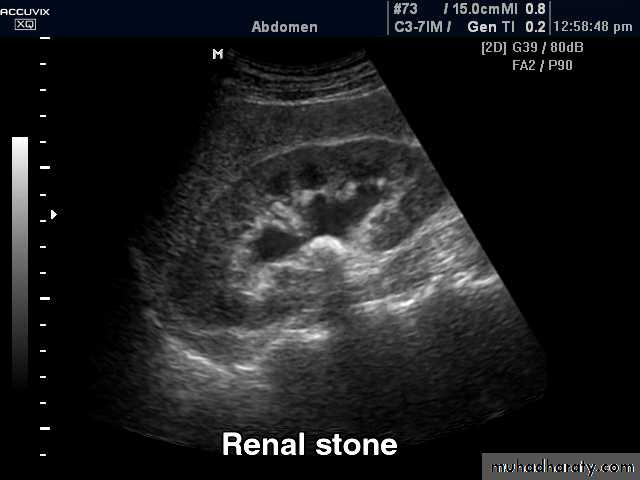

Renal stones